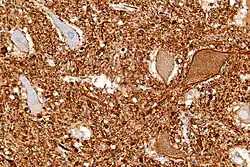

Central chromatolysis

Central chromatolysis is a histopathologic change seen in the cell body of a neuron, where the chromatin and cell nucleus are pushed to the cell periphery, in response to axonal injury.[1][2] This response is associated with increased protein synthesis to accommodate for axonal sprouting. In addition to traumatic injuries, central chromatolysis may be caused by vitamin deficiency (pellagra[3]).